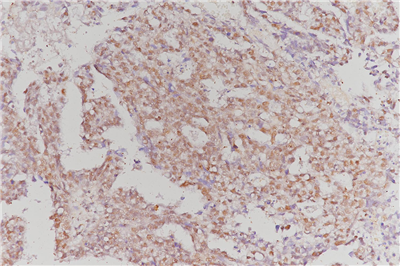

免疫組化是應(yīng)用免疫學(xué)基本原理——抗原抗體反應(yīng),即抗原與抗體特異性結(jié)合的原理,通過(guò)化學(xué)反應(yīng)使標(biāo)記抗體的顯色劑(熒光素、酶、金屬離子、同位素) 顯色來(lái)確定組織細(xì)胞內(nèi)抗原(多肽和蛋白質(zhì)),對(duì)其進(jìn)行定位、定性及定量的研究,稱為免疫組織化學(xué)技術(shù)(immunohistochemistry)或免疫細(xì)胞化學(xué)技術(shù)(immunocytochemistry)。

免疫組化的分類: 免疫組織化學(xué)技術(shù)按照標(biāo)記物的種類可分為免疫熒光法、免疫酶法、免疫鐵蛋白法、免疫金法等。

服務(wù)內(nèi)容:包含抗體,包埋,切片,染色以及拍照。(每個(gè)樣本提供一張照片包含陽(yáng)性面積)加拍另外計(jì)費(fèi)。